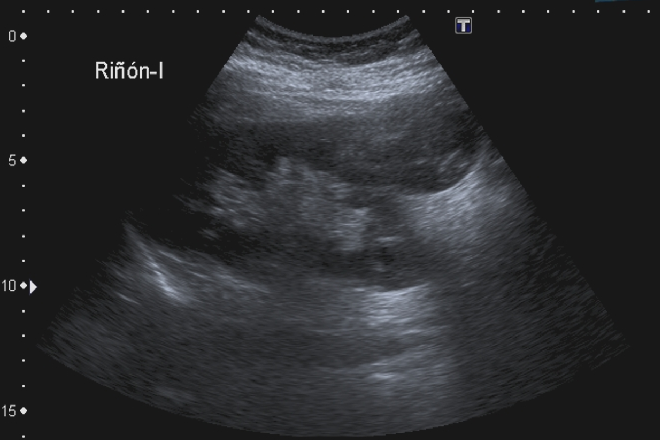

Correlación ultrasonográfica e histopatológica de los tumores de ovario Objetivos. Demostrar el valor del ultrasonido en el diagnóstico de los tumores de ovario, describir desde el punto de vista sonográfico las características de las masas ováricas de acuerdo con su estructura y tamaño. Identificar su